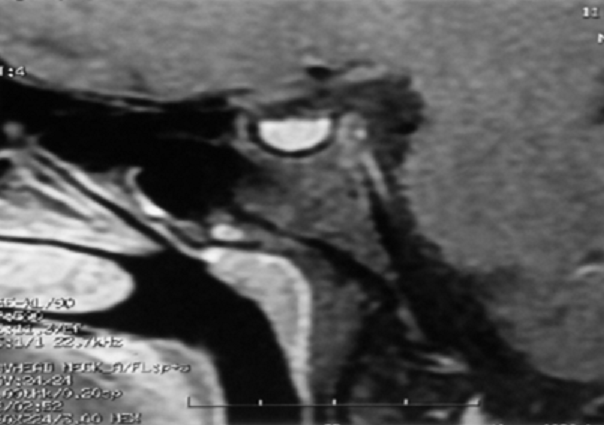

L'hyperprolactinémie, un trouble endocrine fréquent mais largement sous-estimé, peut être due à diverses causes parmi lesquelles figure le traitement par de nombreux médicaments. Les antipsychotiques jouent en particulier un rôle important dans leur survenue. Leur potentiel hyperprolactinémiant est néanmoins variable, mettant en jeu des mécanismes complexes. La fréquence des signes cliniques est le plus souvent corrélée à l'élévation de la prolactinémie mais l'hyperprolactinémie est parfois asymptomatique. Les manifestations cliniques relèvent principalement de troubles sexuels, de troubles du cycle menstruel et de galactorrhée, en plus d'effets à long terme. Ces signes ne sont pas toujours évoqués par les patients ce qui aboutit à une sous-estimation de la prévalence des hyperprolactinémie. Le risque de développer un adénome à prolactine parait étroitement lié à une élévation significative de la prolactinémie au delà de 150 ng/ml. Nous rapportons l'observation de deux patientes qui ont été inclues dans une étude transversale sur 6 mois, portant sur tous les patients suivis à la consultation et traités par un seul antipsychotique depuis 12 semaines à posologie stable. Un dosage de la prolactinémie plasmatique a été réalisé et confirmé par un deuxième dosage en cas d'anomalie objectivée au premier bilan. Une Imagerie par Résonance Magnétique (IRM) hypophysaire a été demandée pour les patients présentant une prolactinémie supérieure à 150 ng/ml. Ces derniers ont bénéficié d'une IRM hypophysaire révélant 2 cas de macroadénomes. Les deux patientes ont bénéficié d'un avis spécialisé des endocrinologues qui ont cosigné la prescription de la Bromocriptine (ParlodelĀ®) avec augmentation progressive de la posologie et monitorage du taux plasmatique de la prolactine dans trois mois ainsi qu'une surveillance des effets psychiatrique vue le risque de décompensation sous dopathérapie. La prescription des agonistes dopaminergiques dans le traitement des hyperprolactinémie doit être prudente dans des cas exceptionnels vue la possibilité de l'aggravation trouble mental sous jacent.